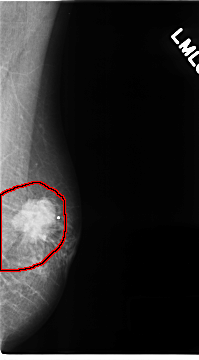

C_0141_1.LEFT_MLO

LEFT_MLO LINES 4672 PIXELS_PER_LINE 2584 BITS_PER_PIXEL 12 RESOLUTION 50 OVERLAY

FILE: C_0141_1.LEFT_MLO.OVERLAY

TOTAL_ABNORMALITIES 1

ABNORMALITY 1

LESION_TYPE MASS SHAPE IRREGULAR MARGINS SPICULATED

ASSESSMENT 5

SUBTLETY 5

PATHOLOGY MALIGNANT

TOTAL_OUTLINES 1

BOUNDARY